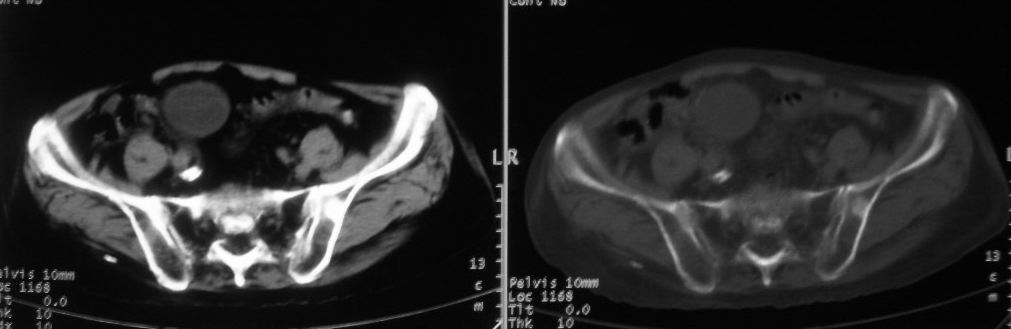

以下是引用深泽交通医院在2008-10-3 15:33:00的发言:[br]前列腺实性增大伴分叶状,与包膜间隙境界不清;椎体松质区间结节样密度影,考虑:前列腺癌,并椎体成骨性转移